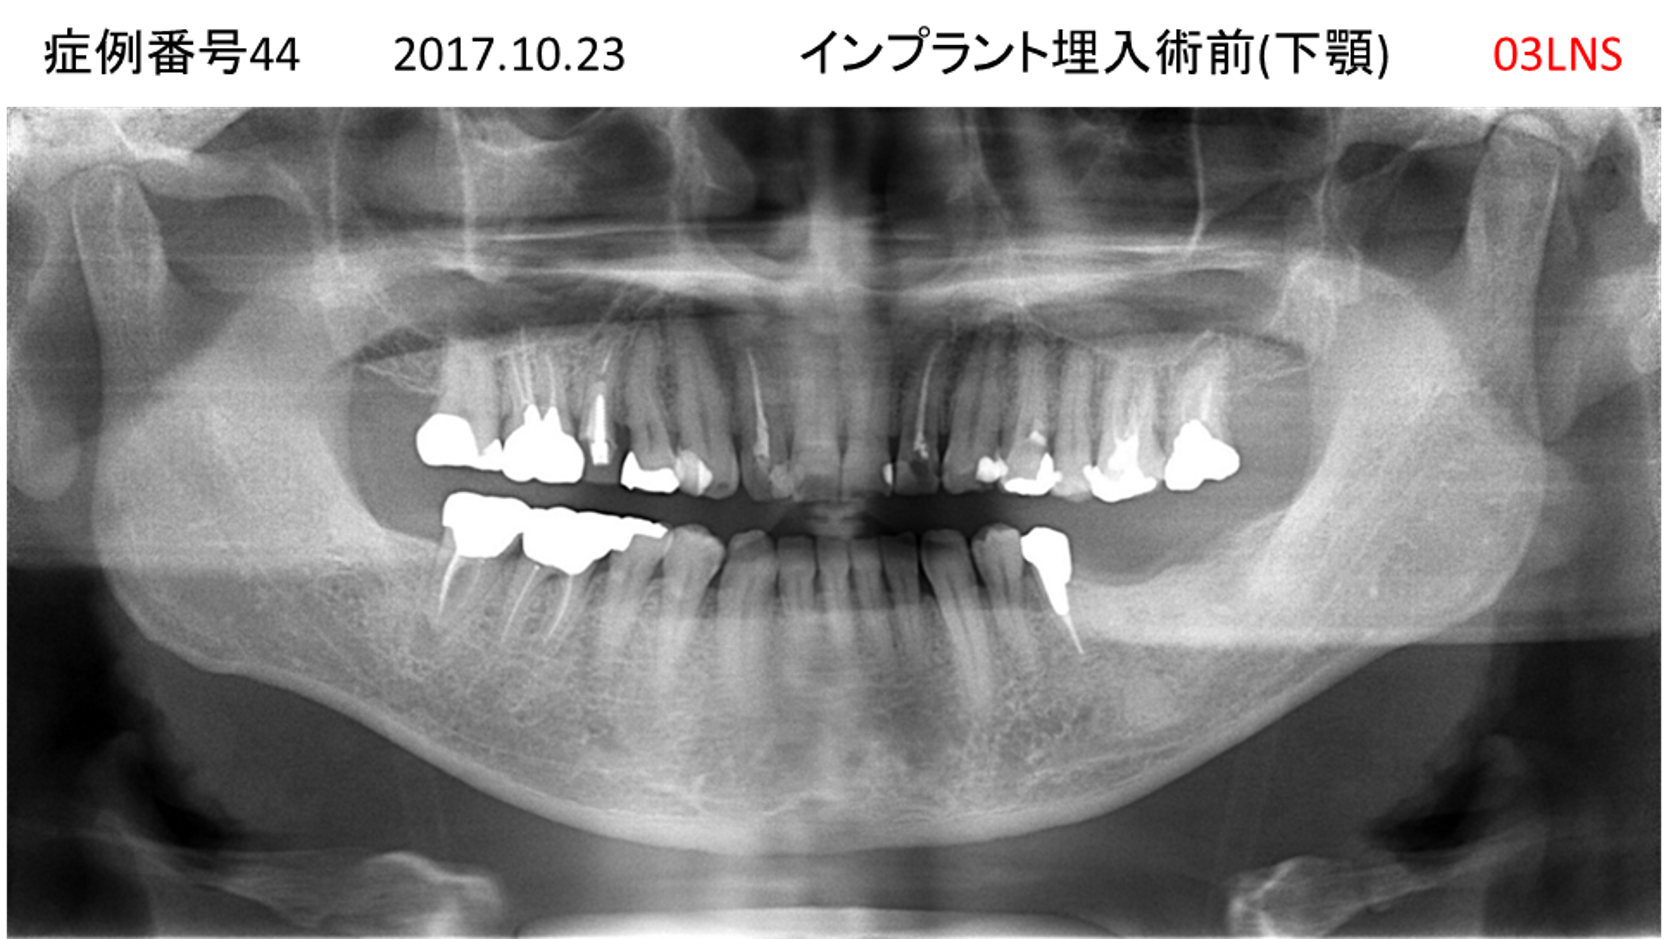

左下の奥歯が痛い患者様のインプラント症例

| 治療名称 |

インプラント |

| 治療費用 |

215万円+税 |

| 治療期間 |

5か月 |

| 患者さんの症状(主訴) |

左下の奥歯が痛い。 |

| 治療内容 |

| 治療結果 |

痛み無く、噛める。 |

| 治療の注意点(リスク/副作用) |

インプラントが壊れたら再治療が必要 |